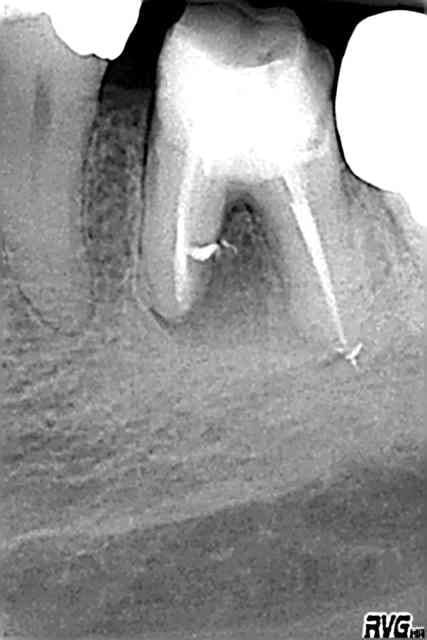

empreinte inlay core + couronne